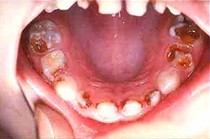

Artritis heilt mit

Borax  Gelenkschmerzen durch Artritis heilen mit

Borax  Knochenschwund (Osteoporose) heilt mit Borax  Karies

wird mit Borax vermindert

Artritis heilt mit Borax [3] - Gelenkschmerzen durch Artritis heilen mit Borax [4] - Knochenschwund (Osteoporose) heilt mit Borax [5] - Karies wird mit Borax vermindert [6] -